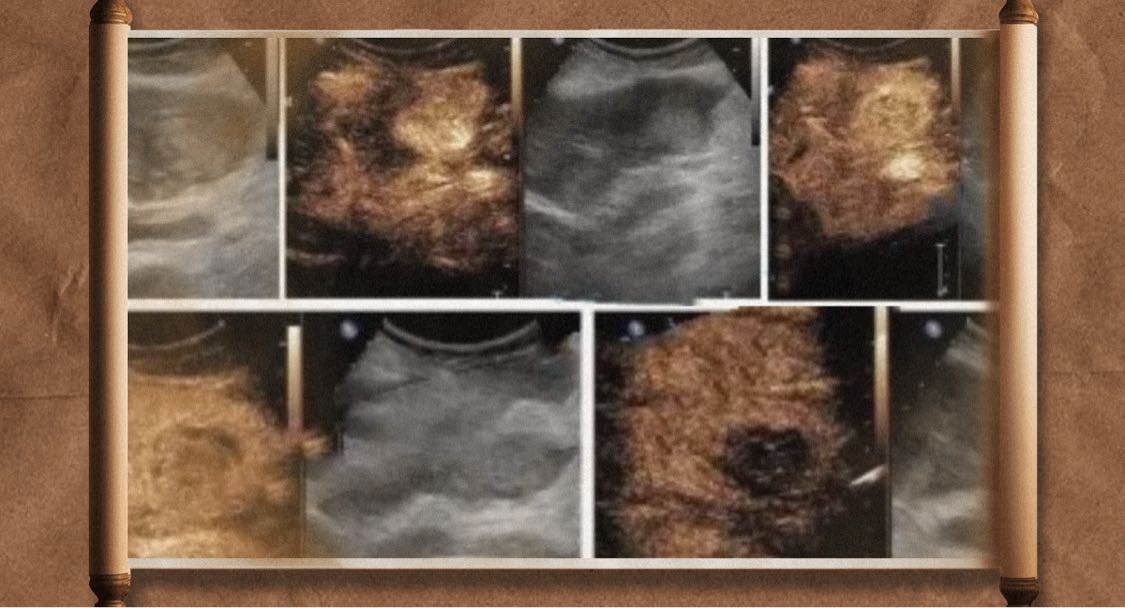

超声造影&常规超声检查&肝脏局灶性病变(FLL)

肝脏局灶性病变

肝脏FLL

肝占位

肝脏超声造影